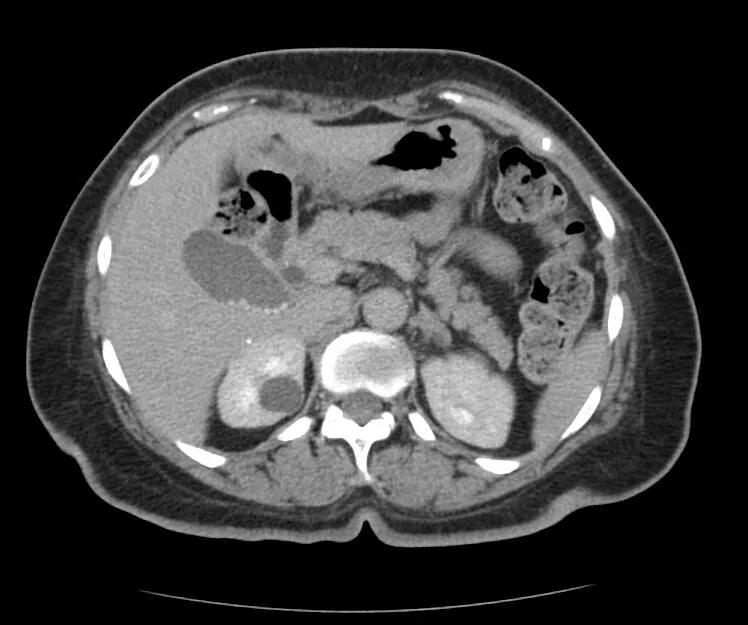

Кисты почек bosniak